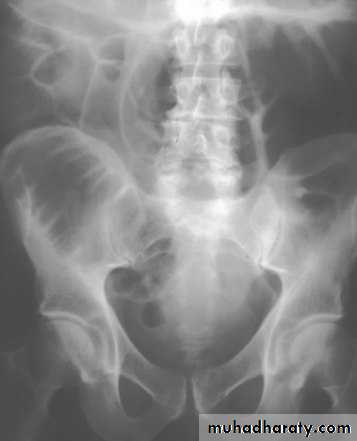

Diagnosis

Abdominal plain films usually diagnostic

Inverted U-shaped appearance of distended sigmoid loop

Largest and most dilated loops of bowel are seen with volvulus

Loss of haustra

Coffee-bean sign à midline crease corresponding to mesenteric root in a greatly distended sigmoid

Sigmoid volvulus – bowel loop points to RUQ

Cecal volvulus – bowel loop points to LUQ

Dilated cecum comes to rest in left upper quadrant

Bird’s-beak or bird-of-prey sign à seen on barium enema as it encounters the volvulated loop

CT scan useful in assessing mural wall ischemia